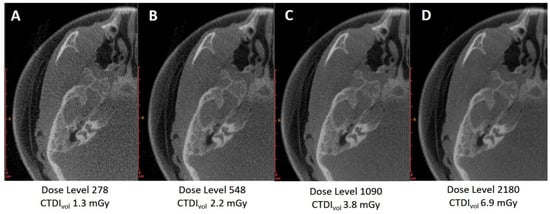

3.1. First Cadaver Head Scan

3.1.1. Variation of Tube Voltage